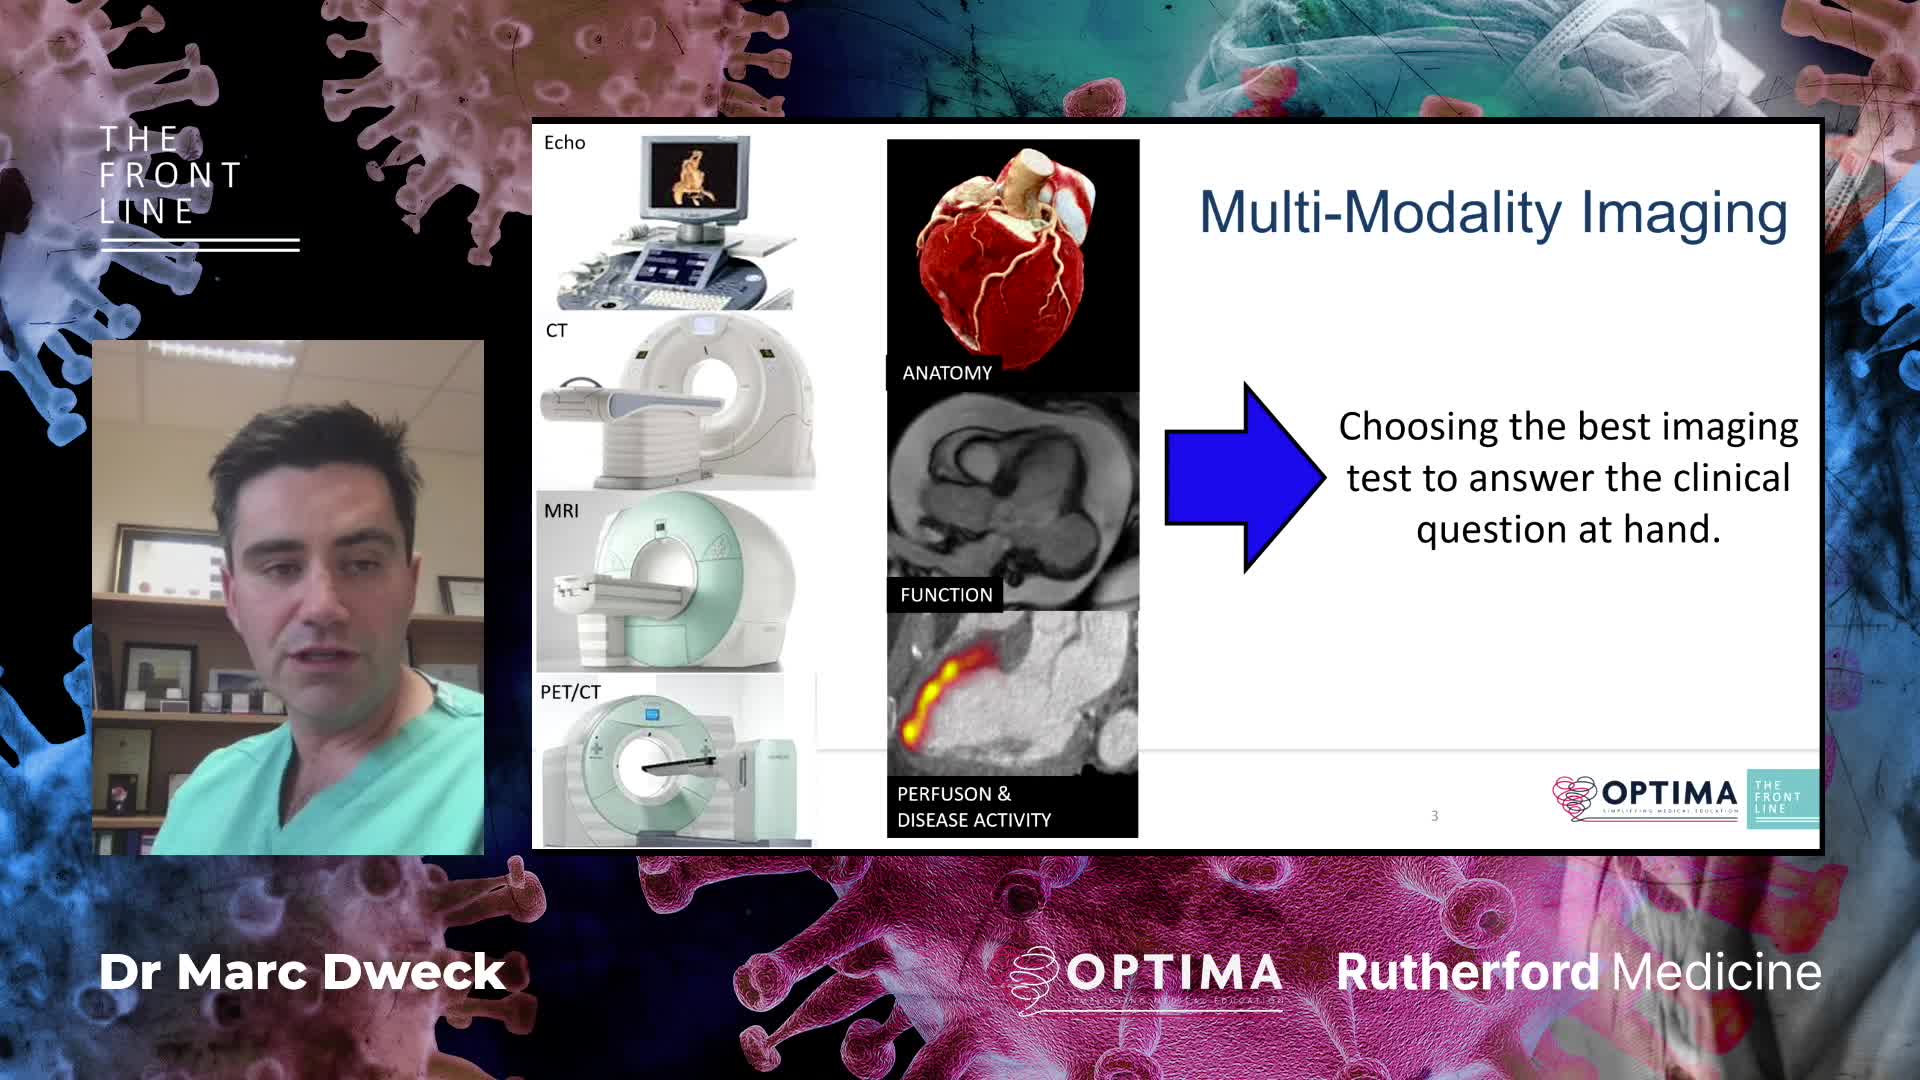

Session 1: Pre-procedure planning – are we lost without a map?